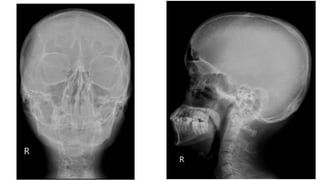

 AP and lateral radiographs of the skull show multiple tiny lucent areas with areas of

sclerosis in between, giving rise to salt and pepper skull appearance.

 Radiographs of both the legs, knees and left humerus show diffuse osteoporosis with

few well defined lytic areas.

 Radiograph of the hand shows osteoporosis with coarse trabeculations of the

phalanges with mild erosions along tteh radial aspect.

HYPERPARATHYROIDISM

FINDINGS

 Osteopenia

 Subperiosteal resorption: classically along radial aspects of phalanges

 Floating tooth

 Subchondral resorption (lateral end of clavicles, pubic symphysis, sacroiliac joints)

 Subligamentous resorption(ischial tuberosity, trochanters)

 Brown tumors(more common in primary)

 Salt and pepper skull

 Rugger jersey spine

 Secondary and tertiary hyperparathyroidism may be associated with osteosclerosis of

renal osteodystrophy and osteomalacia of vitamin D deficiency

 Superior and inferior rib notching may be seen